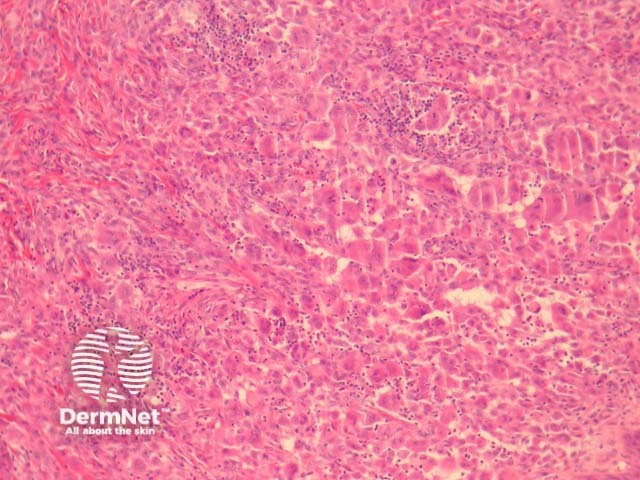

In reticulohistiocytoma, sections show a diffuse infiltration of numerous large, mononucleated or multinucleated histiocytes in the dermis (figures 1-3). There are associated lymphocytes and dermal fibrosis. Characteristically, the lesional cells have a dense pink cytoplasm, variously referred to as “oncocytic” or “ground glass” (figures 2, 3).

Figure 1

Figure 2

Figure 3